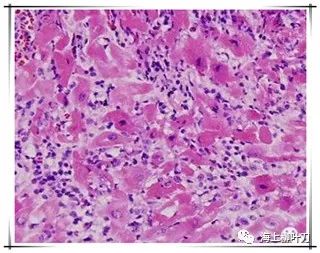

6.這是她的心肌病理切片,放大了100倍。

7.100倍還不是看得很清楚,放大400倍就很明顯了,一個(gè)個(gè)藍(lán)點(diǎn)就是淋巴球。這是很厲害的猛暴性心肌炎,整個(gè)心臟都被淋巴球浸潤了。